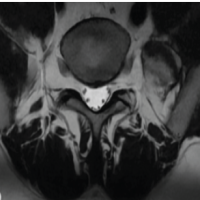

A 79-year-old woman presented with a complaint of a non-painful soft tissue mass in the left axilla of 2-month duration. An incomplete resection of the mass was performed at another institution 6 months before presentation. The histopathologic interpretation of this mass at the outside hospital was that of a low-grade well-differentiated liposarcoma, likely referred to what is now named an atypical lipomatous tumor. On physical examination, there was a large, deep mobile, and non-tender mass adjacent to the chest wall and lateral to the scapula. There was another large, non-tender, bulging mass overlying the posterior surface of the left scapula that did not appear on examination to be contiguous with the axillary mass. The patient was unaware of the posteriorly based mass. An AP radiograph showed focal, well-defined radiolucent defects in the neck and spine of the scapula (Fig. 4). CT and MRI showed a large, multilobulated soft tissue mass around the posterior aspect of the scapula and deep to the supraspinatus and infraspinatus muscles. The mass perforated the scapula from posterior to anterior and extended laterally into the axilla; it was contiguous with the axillary mass (Fig. 5a and b). The portion of the mass over the posterior aspect of the scapula was homogenous and hyperintense on T1 and T2 pulse-weighted sequences, whereas the axillary mass was more heterogeneous and somewhat more hypointense on T1 pulse-weighted sequences.

Figure 5: Case 3 computed tomography (CT) and magnetic resonance imaging [MRI] T1-weighted – axial. (a) CT demonstrates a large multilobulated low attenuation mass abutting the posterior aspect of the scapula which has eroded through bone to the anterior aspect of the scapula and which extends laterally into the axilla (red arrow). (b) T1-weighted MRI demonstrates a large multilobulated fatty mass eroding into and through the posterior aspect of the scapula that on the inset is seen to be contiguous with the axillary mass (red arrow).